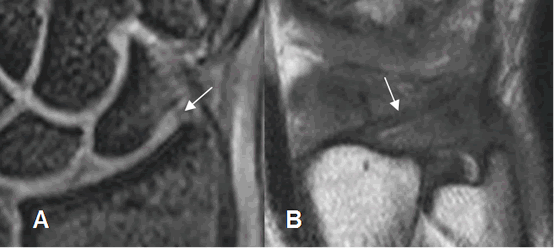

El FCT se identifica como una estructura bicóncava y en forma de corbatín, hipointensa en todas las secuencias. Se pueden ver sus inserciones en el radio y cúbito.

Sus componentes se identifican con la RM. El menisco, disco y ligamentos ulnopiramidal y ulnosemilunar se aprecian en vistas coronales. Los ligamentos radioulnar dorsal y volar se visualizan en el plano axial. (2). (Fig 22 y 23).

El menisco es una estructura hipointensa, con leve aumento normal de la señal sobre la inserción ulnar. (2).

Fig 22. Complejo del FCT normal.

A: RM coronal en T2. Cartílago (Flecha delgada), menisco homólogo (Flecha gruesa) y tendón del extensor ulnar del carpo. (Punta de flecha).

B: RM coronal en T2. Cartílago con su inserción radial (Flecha delgada) e inserción ulnar (Flecha gruesa).

Fig 23. Complejo del FCT.

A: RM axial en T1. Ligamentos radioulnar anterior (Flecha delgada) y radioulnar posterior (Flecha gruesa).

B: RM coronal en T2. Ligamentos ulnosemilunar (Flecha delgada) y ulnopiramidal (Flecha gruesa).